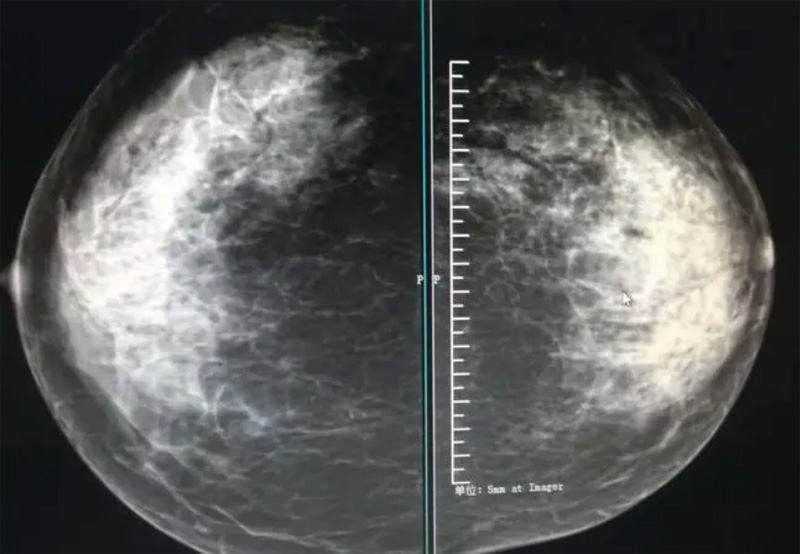

乳腺DR攝影體位有頭尾位及內外側斜位,

乳房在片子的中央,乳頭切線位,可見小部分胸大肌,內側乳腺組織應全部包括在片中,外側乳腺組織盡可能包括在片中。一張好的MLO位圖像顯示如下:乳房被推向前上,乳腺實質充分展開,胸大肌可見,較松弛,下緣達到乳頭水平,乳頭在切線位,部分腹壁包括在片中,但與下部乳腺分開,絕大部分乳腺實質顯示在片中。乳腺組織外緣可見乳頭的輪廓;乳腺后方的脂肪組織被很好地顯示出來,乳房無皺褶。對于CC位及MLO位顯示不良或未包全的乳腺實質,可以根據(jù)病灶位置的不同選擇以下體位:外內側位(LM)、內外側位(ML)、內側頭尾軸位(MCC)、外側頭尾軸位(LCC),尾葉位(CLEO)及乳溝位。在臨床實踐中,對于常規(guī)體位上發(fā)現(xiàn)的異常改變,可以進一步采取一些特殊的攝影技術,包括局部加壓攝影、放大攝影或局部加壓放大攝影技術。

2、規(guī)范觀圖程序:屏幕軟閱讀或在專用日光觀片燈下膠片閱讀,后者應同時準備白熾強光燈及觀片放大鏡。注意雙側乳腺配對觀察,推薦雙眼橫向掃描,進行雙乳相同部位圖像比較分析。

3、乳腺實質背景的確定:觀察乳腺實質與脂肪的構成比例,了解乳腺實質類型,以判斷對某些乳腺攝影征象敏感性的影響,有利于確定乳腺攝影對疾病的診斷價值。